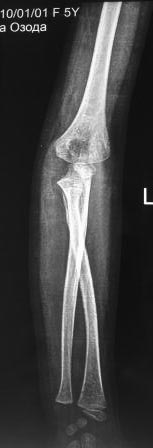

Обратилась девочка 2010г.р., 8 месяцев назад в результате падения на руку получила травму, гипсовая повязка , которую сняли через неделя и дальше не лечилась, со слов матери постепенно нарастает деформация.

Объективно отмечается волярное выбухание головки лучевой кости, и гиперэкстензия в локтевом суставе, функция почти не нарушена, супинация и пронация сохранены. Какой-то чувство, что возможно была разгибательный переломо-вывих Монтеджа. Фото руки и Р-снимки представляются.

В плане корригируюшая остетотомия на уровне с-в/з локтевой кости с восстановлением дуги локтевой кости ( сначала измерить другую локтевую кость), фиксация - или пластина или и/м штифт., вправление вывиха головки луча, восстановление кольцевидной связки из местных тканей, временная фиксация спицей к локтевой кости.-это пока предварительно то, что пришла на ум сейчас!